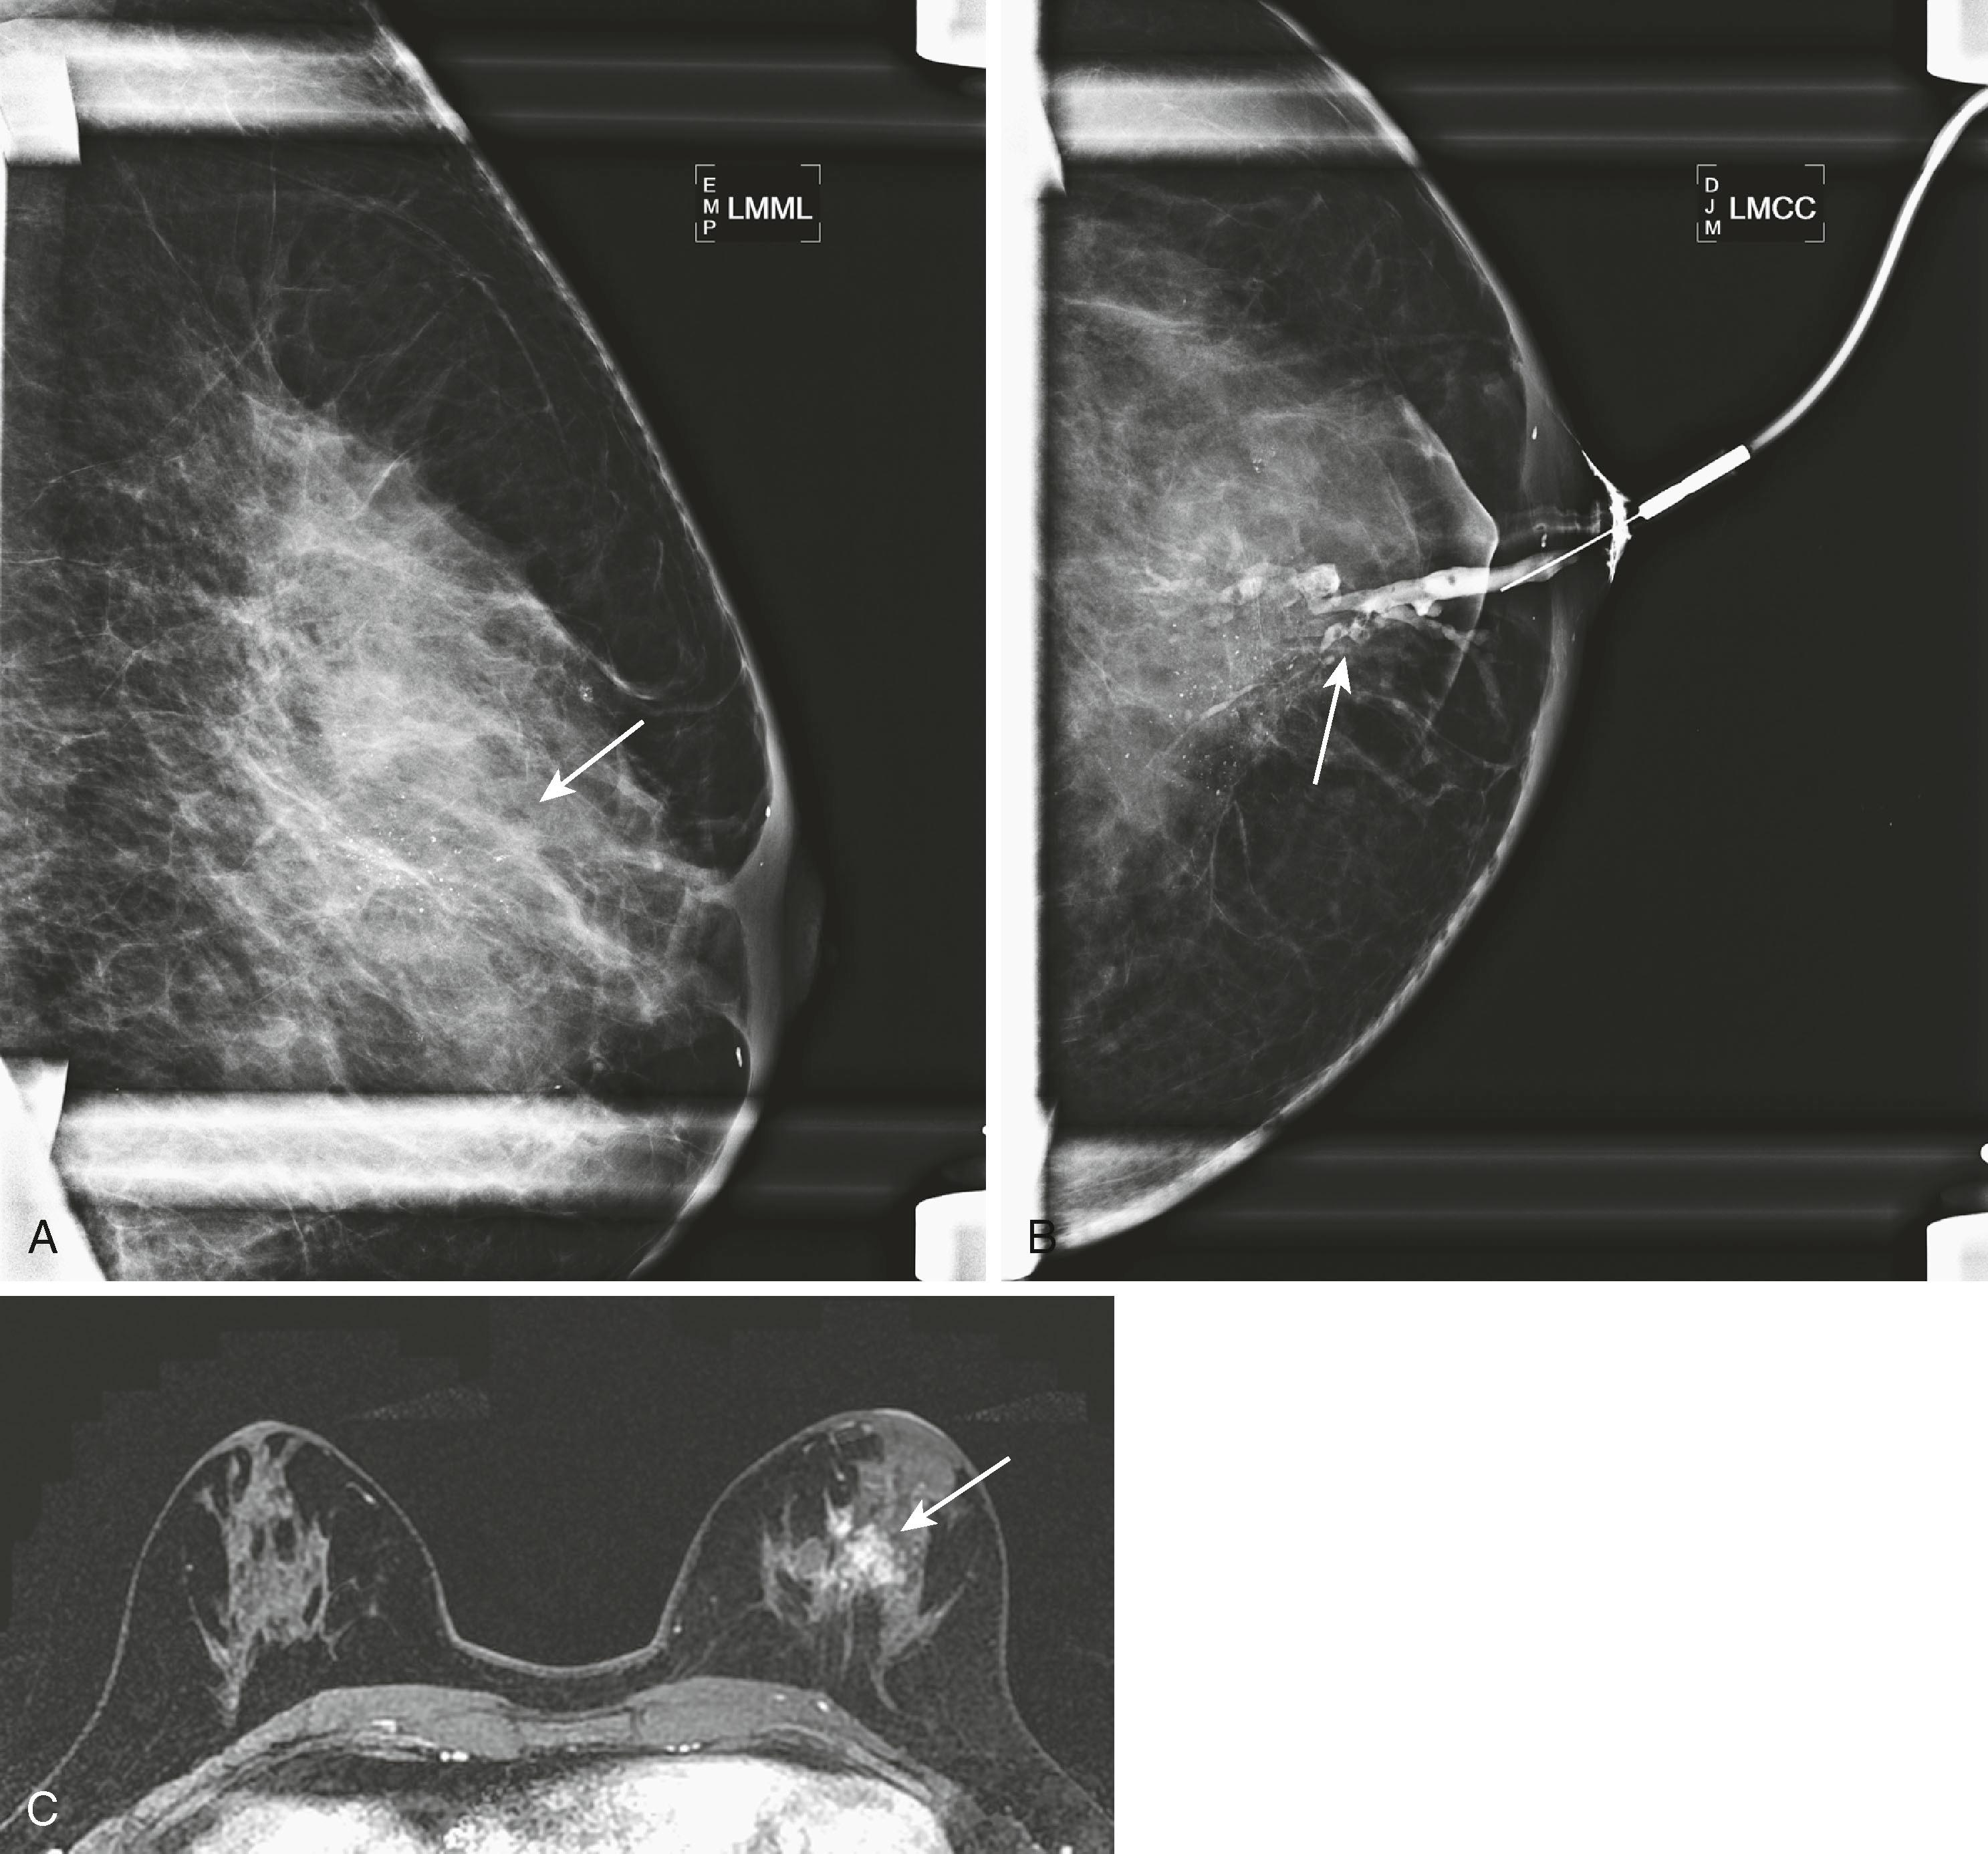

High-risk lesions such as atypical ductal hyperplasia (ADH) have a variable MRI appearance. The kinetic features are variable, ranging from washout to progressive. Contrast enhancement is thought to be the result of increased microvessel density and/or capillary permeability. The morphology is typically nonmass-like; however, sometimes these lesions can present as masses. When ADH is diagnosed by MRI-guided biopsy, recent literature suggests an upgrade rate of approximately 30% to malignancy. This is considerably higher than the upgrade rate of approximately 19% for stereotactic biopsy. According to Liberman and colleagues, this may be related to the fact that the women undergoing MRI are at a higher risk than those routinely undergoing mammography. Fig. 8.26 demonstrates one appearance of ADH. It is nonmass with a predominantly plateau pattern enhancement. Similar to high-risk lesions, the kinetic pattern of DCIS is variable. The typical morphological appearance of DCIS is described as nonmass clumped linear or segmental enhancement. Occasionally, an enhancing ductal branching pattern or filling defects within fluid-filled ducts can be identified ( Fig. 8.27 ). Similar to mammography and ultrasound, DCIS rarely may present as a mass on MRI. It is not currently possible to reliably predict whether there is a coexistent invasive component or the exact histological type of DCIS based on the morphology or kinetic characteristics. The sensitivity of MRI for detecting DCIS is lower than for invasive breast cancer, with reported sensitivities ranging from 77% to 96%. The specificity is considered to be similar to that of invasive cancer. MRI is better at depicting high-grade DCIS than low-grade disease. It is better at demonstrating high-grade DCIS without necrosis than mammography because DCIS is most frequently detected when the mammogram demonstrates calcifications. Unfortunately, it is well known that microcalcifications identified mammographically are often nonspecific. Because MRI does not detect DCIS by imaging the calcium, it is difficult at times to make a direct correlation between the mammogram and the MRI; therefore, at present, MRI and mammography are complementary tests. Fig. 8.28 shows malignant calcifications on a mammogram and the MRI demonstrates malignant morphology typical of DCIS.

Fig. 8.28, ( A ) Spot magnification 90-degree mammogram shows pleomorphic calcifications in a segmental distribution (arrow) on left mediolateral 90 degree view (LMML). ( B ) Ductogram showed ductal dilatation with filling defects interspersed among the calcifications (arrow) on left craniocaudal view (LMCC). ( C ) Magnetic resonance imaging shows a corresponding area of nonmass enhancement (arrow) , which was ductal carcinoma in situ.